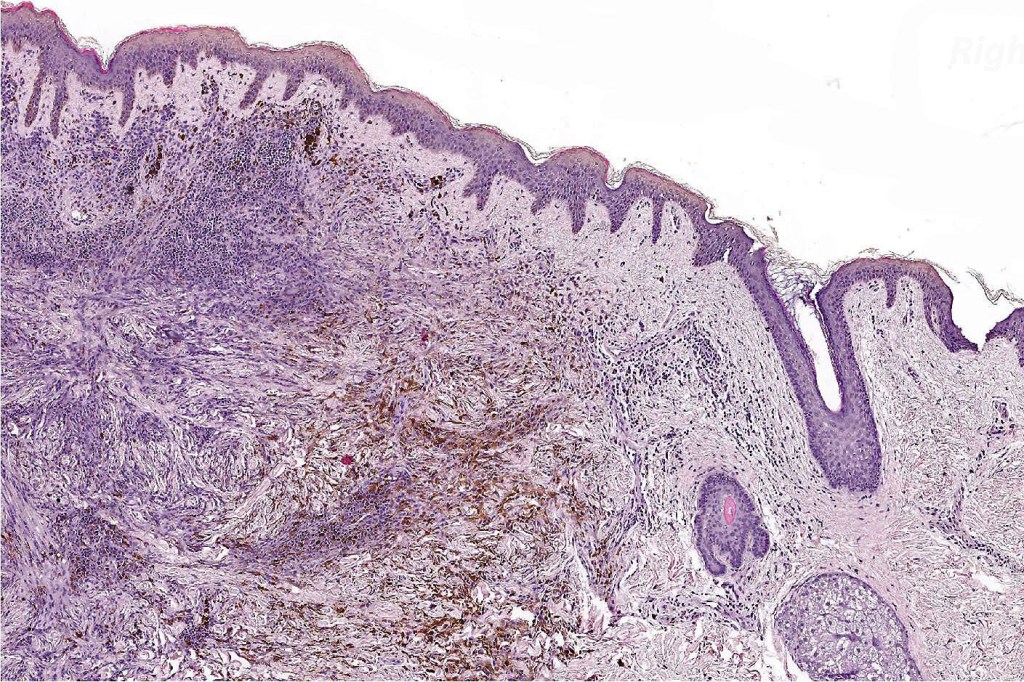

Combined congenital & blue nevus (same case as the clinical photographs coursty of Dr. Antonina Kalmykova